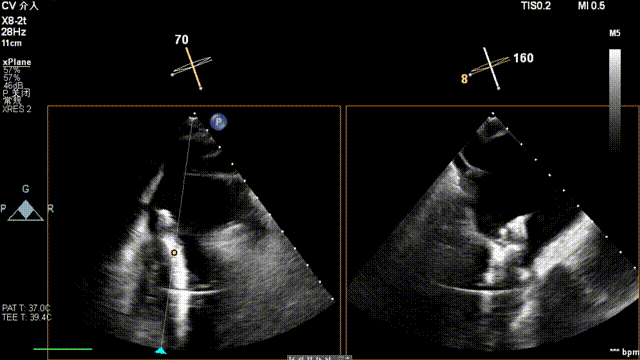

术前超声

患者为原发性二尖瓣反流(DMR),收缩期可见二尖瓣反流信号,反流位于 2 偏 3 区,基线期二尖瓣反流程度4+。

前叶长度 15.7mm,后叶长度 12.7mm,后叶脱垂宽度13.9mm,脱垂高度4.76mm, 瓣环直径37.1mm,VC:4*7mm, MVA约4cm² 。瓣叶质地较差,腱索断裂、后瓣叶脱垂。